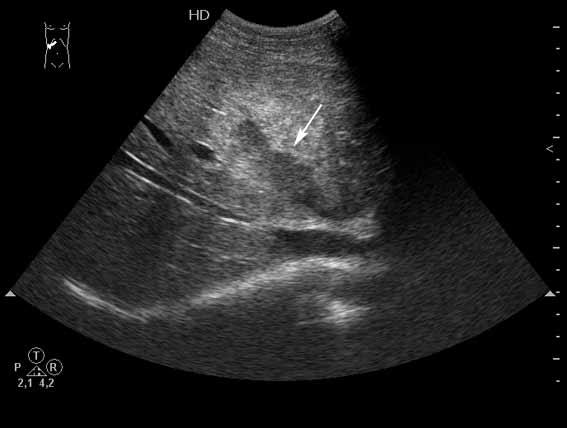

Разрыв печени у пациента 26 лет

При поступлении